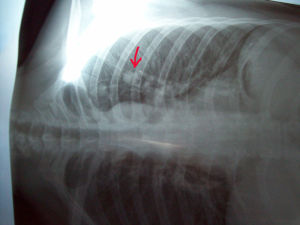

肺結節病的主要病變為非特異性肺泡炎、非乾酪樣壞死性肉芽腫及病變晚期不同程度的肺間質纖維化。其肉芽腫在病理形態上與結核性肉芽腫相似,但具有以下特點:肉芽腫大小較一致,各自境界清楚,少有融合;結節中心無乾酪樣壞死,多核巨細胞可為Langhans型,也可為異物型,結節周圍浸潤的淋巴細胞較少;巨細胞漿中可見到兩種包涵體,即星形體(asteroid body)和Schaumann小體。星形體為胞漿內一個透明區中含有強嗜酸性的放射狀小體;Schaumann小體是球形同心層狀結構,其成分為含鐵和鈣的蛋白質。

本病的早期病變為單核細胞浸潤伴纖維母細胞增生的非特異性肺泡炎,進一步可發展為非乾酪樣壞死性肉芽腫,病灶內富含網狀纖維,結節易於纖維化。肉芽腫可發生於支氣管和血管周圍的間質中,也可發生於肺泡間隔。病變晚期肺間質發生不同程度纖維化,並可累及胸膜。